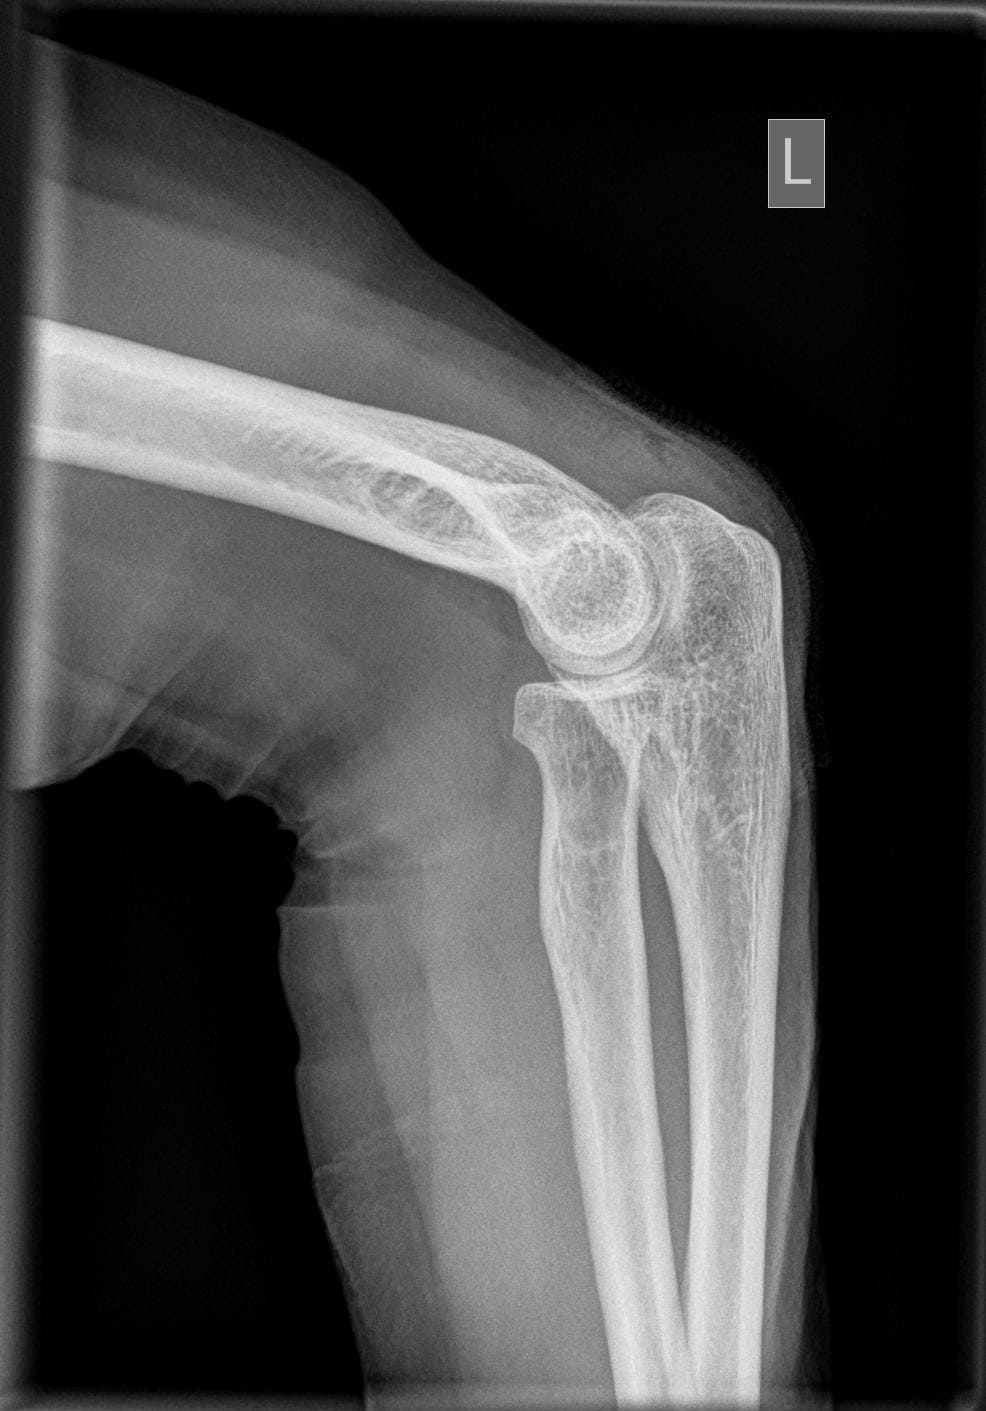

Ellenbogen seitlich

Fehler

Der distale Oberarmteil ist schräg projiziert, d.h. die beiden Gelenkrollen überdecken sich nicht, sondern erscheinen über- resp. untereinander. Ursache hier ist die Schrägprojektion bei hängendem Oberarm.

Abhilfe

Es müssen Oberarm und Unterarm auf Schulterhöhe waagerecht aufliegend.

Der distale Oberarmteil ist schräg projiziert, d.h. die beiden Gelenkrollen überdecken sich nicht. Hier gibt es eine Doppelkontur der Gelenkrollen in Richtung Handgelenk hin. Ursache hier ist die Schrägprojektion, da Unterarm nicht unterpolstert wurde.

15°-Keil oder Handgelenk der Gegenhand unter den betroffene Unterarm/Handgelenk legen.